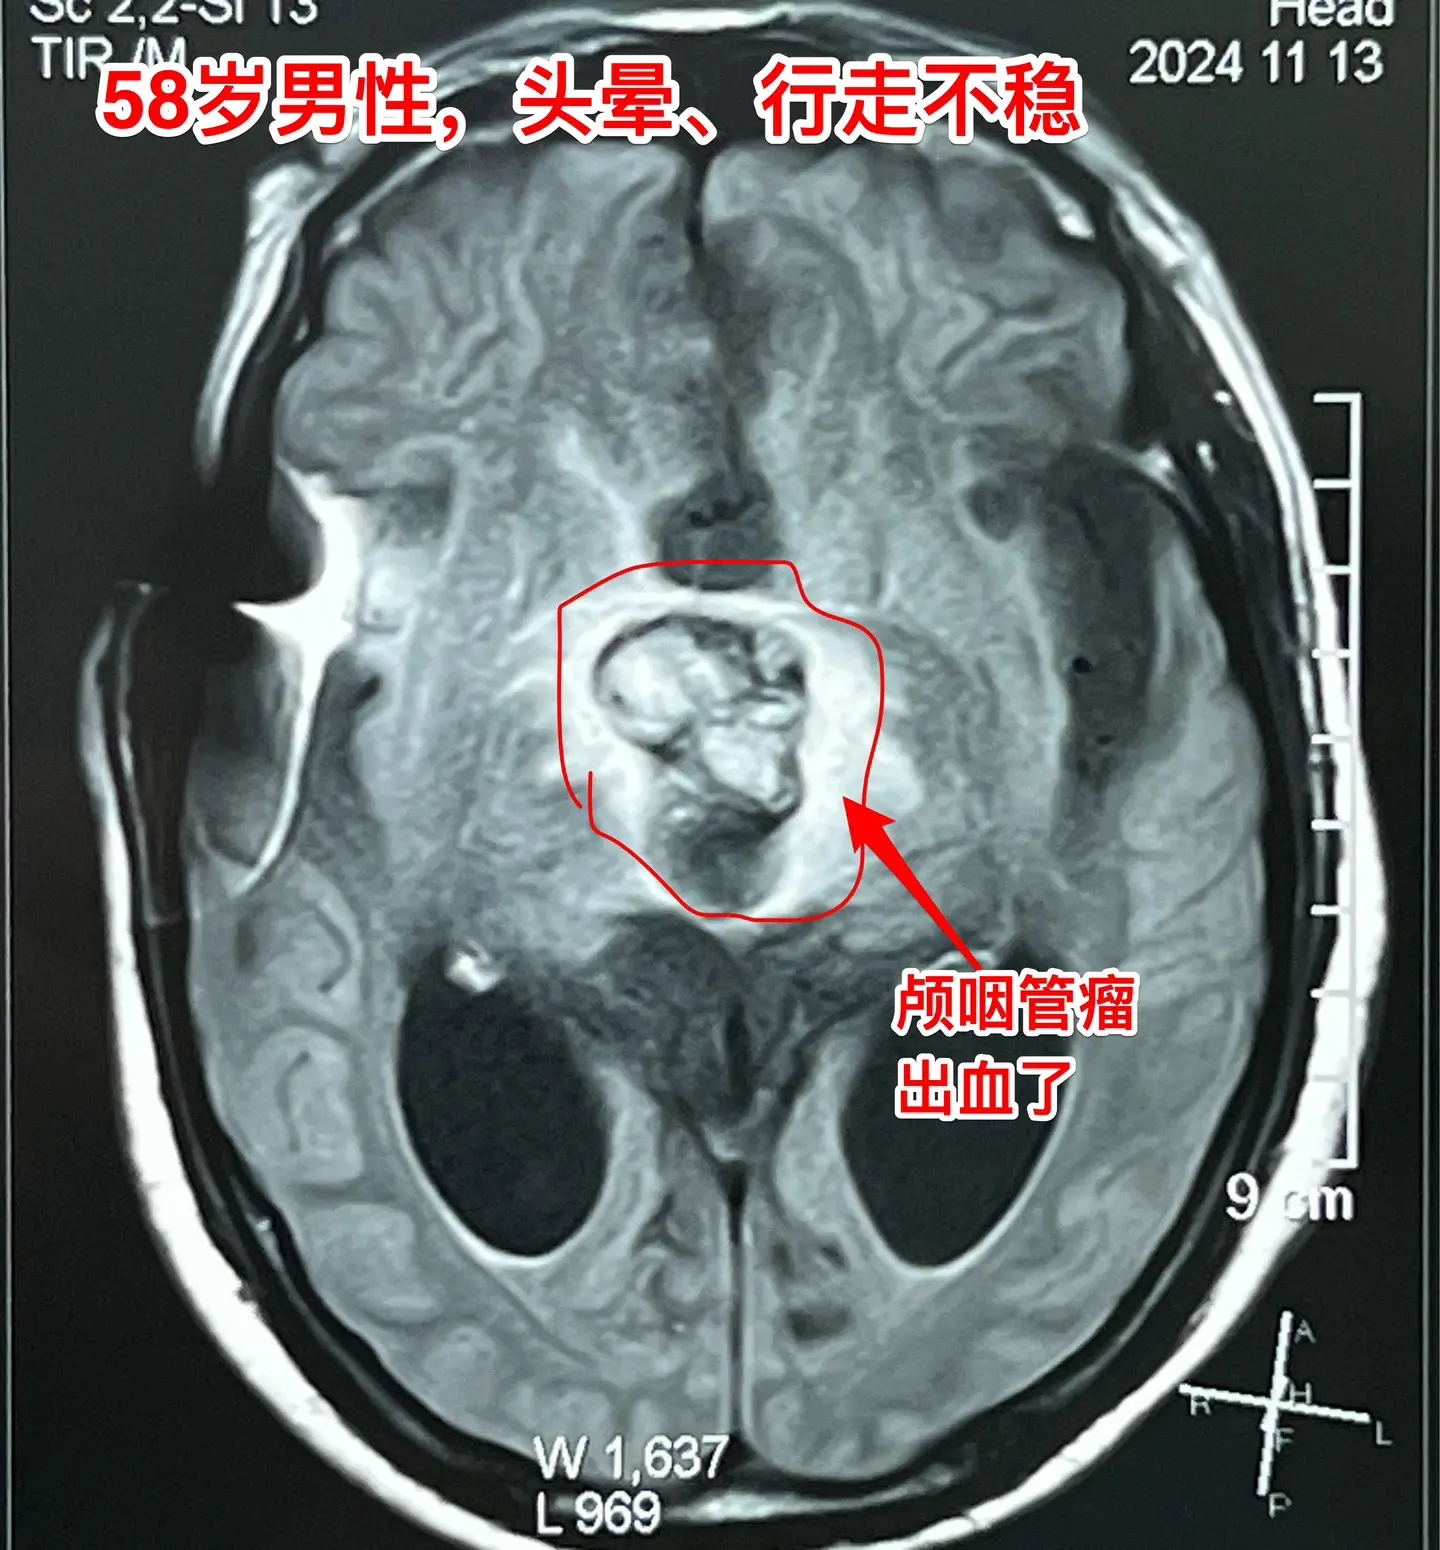

颅咽管瘤内出血(瘤卒中)属于罕见现象。有些脑部肿瘤容易出血,称之为瘤卒中,比如垂体瘤(属于良性肿瘤)和高级别胶质瘤,而颅咽管瘤发生瘤卒中的可能性却很小很小。 58岁的南通市男性,九年前体检发现鞍区病变,无任何症状,一直没有做任何治疗。四个月前开始出现头晕、行走不稳,同时还有思维糊涂,有一次癫痫发作。这次到医院检查就发现鞍区肿瘤增大了,而且导致了脑积水。 2024.9在外院作了脑积水的分流手术,没有切除肿瘤。手术后行走不稳症状有好转,但是思维糊涂症状却越来越严重,有时感头痛。 2024.10到我科住院,病人不仅仅是思维糊涂,还出现头痛症状。行头部CT检查提示颅咽管瘤内出血了。 2024年11月14日作了开颅手术。切除肿瘤过程中可以看见肿瘤内有陈旧出血。病理报告为乳头型颅咽管瘤。乳头型颅咽管瘤出现瘤卒中的概率是很低的,我曾经在2008年报告了一例。造釉细胞性颅咽管瘤几乎不出现瘤卒中。 这个病人的脑积水是由颅咽管瘤引起的,所以,切除颅咽管瘤后脑积水自然就会缓解。希望他的症状会越来越改善。颅咽管瘤脑积水瘤卒中